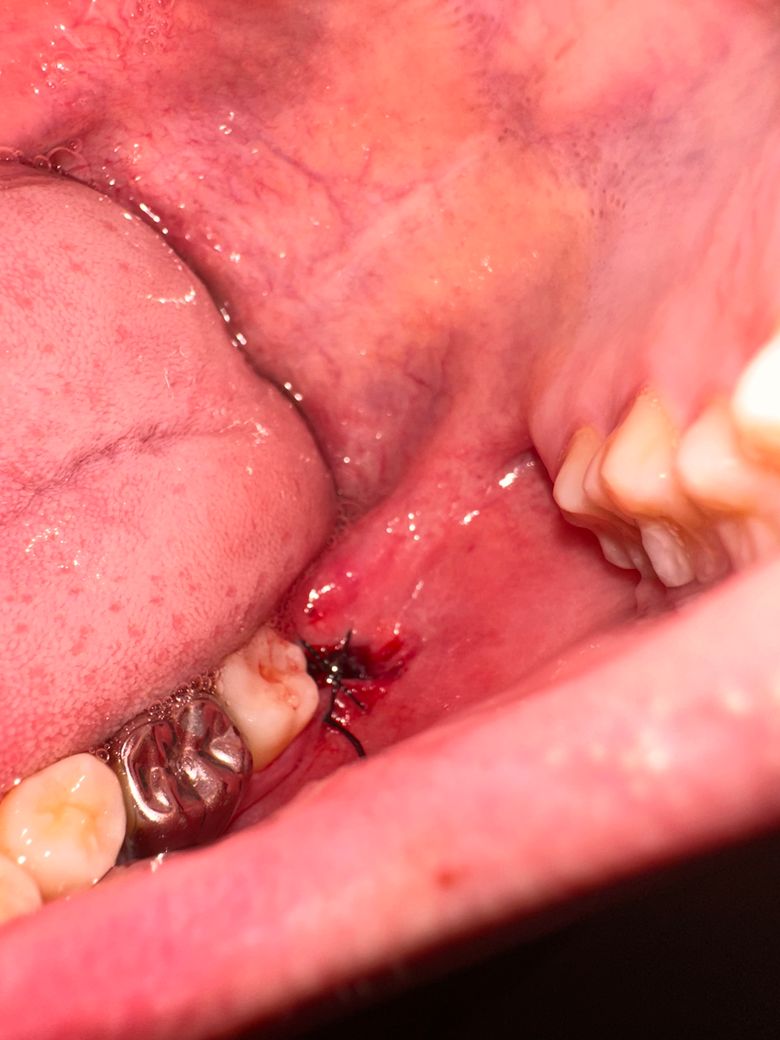

매복사랑니 발치 후 꿰멘것이 벌어져있어요..

사진첨부하겟습니다

• 1번 째 사진

원래 저정도 실밥으로 봉합을 해놓습니다. 실밥이 벌어진게 아니니 너무 걱정하지 않으셔도 될것같습니다.

꿰멘 것은 붓기가 조금씩 빠지면서 벌어져 보일 수 있습니다. 특별히 문제될 것은 없으며 신경안쓰셔도 됩니다.

봉합은 아직 잘 있습니다 풀리거나 하진 않았습니다 해당 부위로 음식물이 낄 순 있으나 물 가글 잘 해서 빼주기만 하면 문제 없습니다